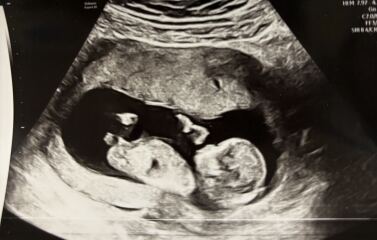

Has anyone used early glimpse for a gender prediction based on nub theory and it been right? I got this from them and really hoping it’s right! 🤞🏻I have included the original scan and a couple others I have too.

Nub theory - early glimpse